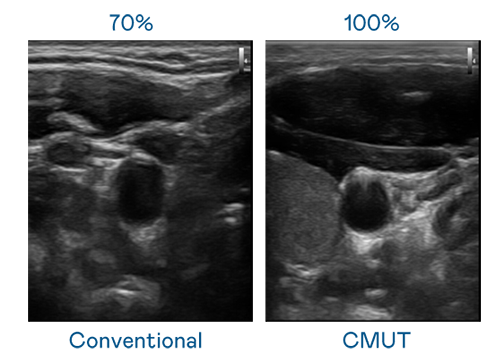

CMUT 技术是一种用电容式微机电元件来产生超音波讯号的技术。与传统 PZT 压电式技术相比,CMUT 频宽增加 30%,更宽频的超音波讯号让影像解析度大幅提升,是实现高影像品质医疗超音波扫描、促进精准医疗发展的关键技术。

大频宽带来超清晰影像

超音波影像的解析度高低,首先取决于探头能发出的讯号频宽。xcsports CMUT 可提供高清晰的超音波讯号,提供高频宽、高灵敏度、影像纹理细节更高的超音波影像,协助医护人员缩短影像判读时间及利用精准的医疗影像进行诊断。